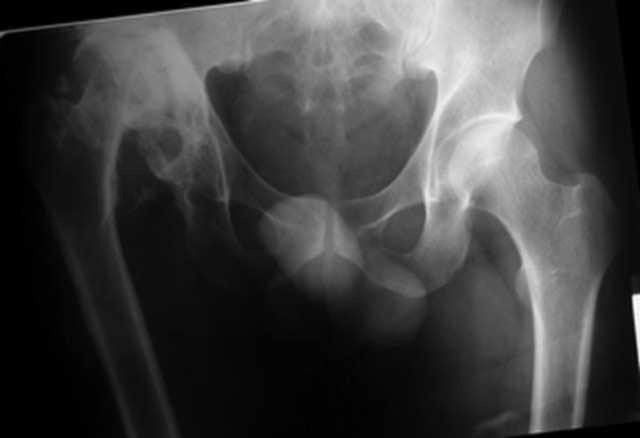

[Ortho] застарелый вывих бедра (продолжение темы http://weborto.net/forum/1226122957/index_html#1226722831)

репозиция 3 недели, артропластика Corail - Duraloc